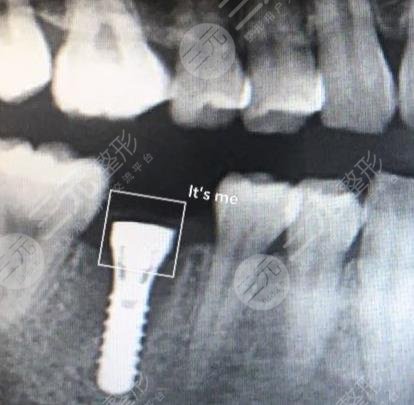

Surgical Procedure: Dental implants

After some struggle, I finally decided to do dental implant surgery, and then I also chose a more reliable dental hospital, after coming to the hospital, the doctor introduced me to a lot of relevant knowledge, and also understood what dental implants are all about, after understanding what is going on, the doctor checked my overall situation, I met the standards for dental implants, and went to the hospital for dental implant surgery on the second day, and injected anesthetics at that time, so the whole operation process will not produce any pain, After the surgery, the local swelling may be more obvious, I was more worried about the fear of tooth bleeding, but the situation is not very bad, about 2~3 days The whole swelling was relieved, and there was no bleeding.